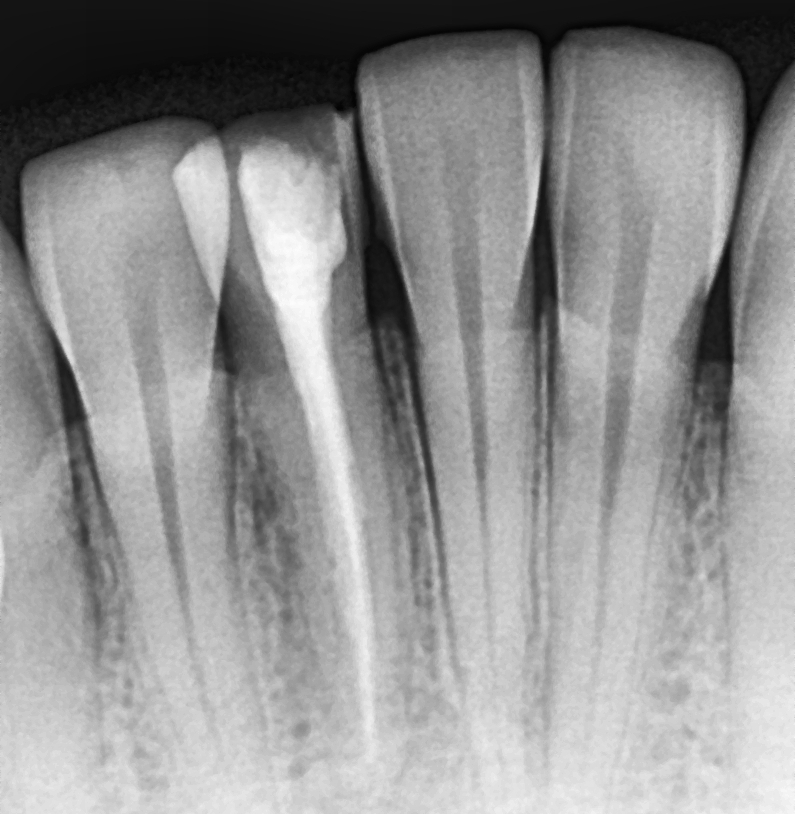

• A diagnosis is made for the tooth with percussion, palpation and cold tests and an x-ray.

• Measurements of the length of the root canal is noted and take x-rays to confirm the length. Ensuring that the entire length of the root canal is cleaned.

Gallery